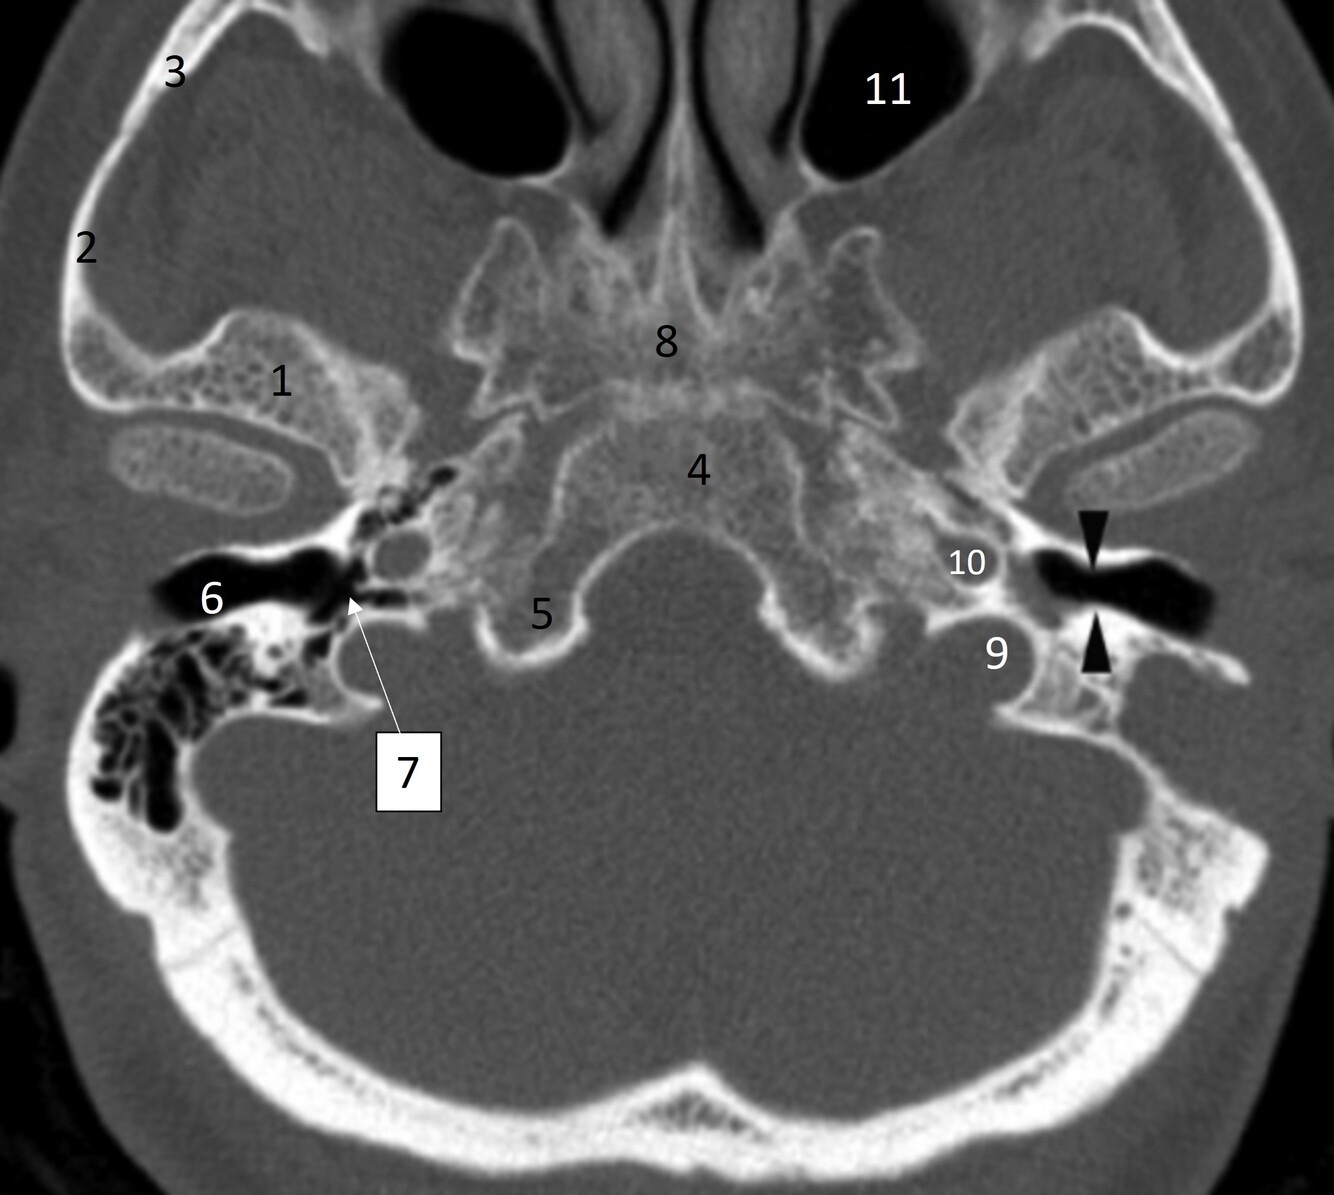

20

Label 36,37,46,62

A

36=Rt. Inferior nasal concha

37=Lt. Inferior nasal meatus

46=Lt. carotid canal

62= Lt. EAM

22

What narrowing are the black arrowheads pointing at?

Isthmus of Rt EAC